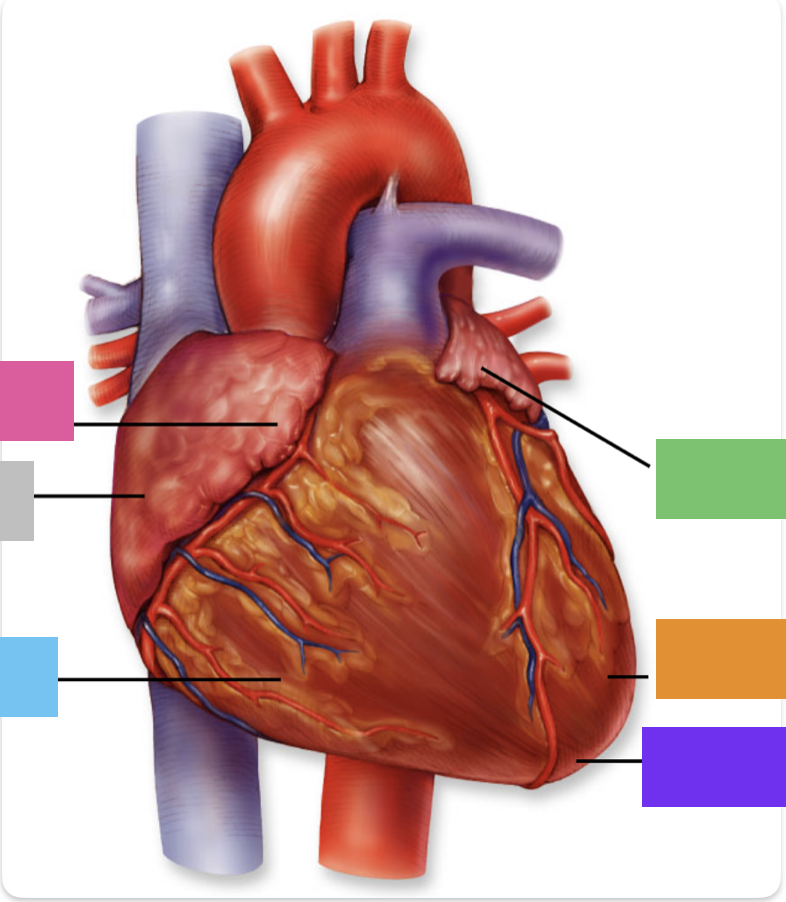

light purple

base

purple

apex

grey

right atrium

pink

right auricle

green

left atrium

green

left auricle

blue

right ventricle

orange

left ventricle

green

coronary (atrioventricular) sulcus

green

anterior interventricular sulcus

red

right coronary artery

yellow

posterior interventricular artery

green

left coronary artery

blue

anterior interventricular artery

pink

circumflex artery